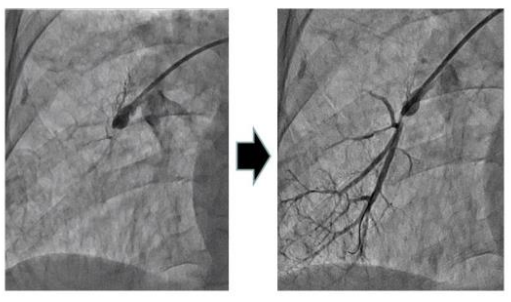

グループ4に分類される慢性血栓塞栓性肺高血圧症(CTEPH)は固くなった血栓(器質化血栓)により肺動脈が細くなったり、閉塞したりする病気です。その原因はいまだ解明されておらず、特定疾患治療研究事業対象疾患(指定難病)に指定されています。

以前はCTEPHに対しては手術(肺動脈血栓内膜摘除術)以外に有効な治療法がありませんでしたが、近年になりカテーテルによる治療(経皮的肺動脈バルーン拡張術:BPA)が可能となり、当院でもカテーテルによる BPA を行っております。安全性を重視し何度かにわけてのカテーテル治療が必要になりますが、通常病態の場合、当院では 3-5 セッションで治療が完遂できるように治療する方針で取り組んでおります。

肺動脈バルーン拡張術